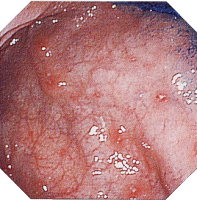

内視鏡所見

縦走潰瘍 敷石像 不整形潰瘍

クローン病画像 クローン病画像 クローン病画像

提供:牧山和也先生

(註2)縦走潰瘍とその周辺小潰瘍間の大小不同の密集した粘膜隆起であり、密在した炎症性ポリポ−シスもこれに含める。虚血性大腸炎の場合、肉眼標本上で浮腫や残存粘膜島が敷石像類似の所見を呈することがあるが、その高さは低く、発赤調が強い。